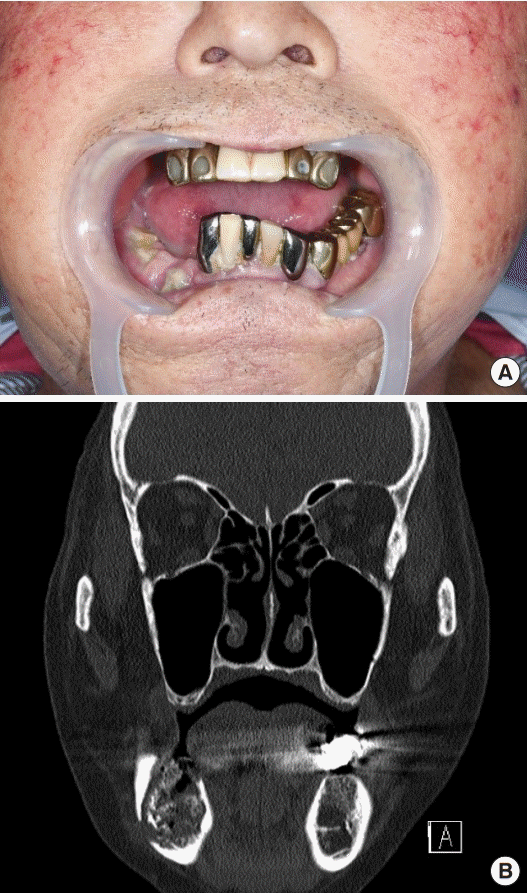

From www.cureus.com

Cureus Maxillary Osteomyelitis in a Patient with Pansinusitis and Chronic Osteomyelitis Jaw Icd 10 Chronic osteomyelitis develops after months to years of per sistent infection and may be characterized by the presence of necrotic bone. Osteomyelitis (om) of the jaw is a rare medical condition. In this review, we provide a descriptive analysis of the experience with this condition at a single tertiary health care centre. The code is valid during the current. The. Chronic Osteomyelitis Jaw Icd 10.